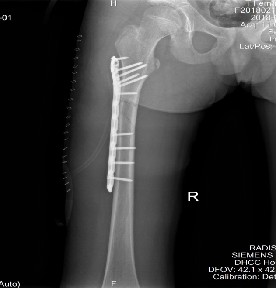

✱骨外科:四肢骨折手法复位外固定术、四肢骨折开放复位内固定术、骨髓炎开窗引流术、人工全髋关节置换术、人工股骨头置换术、股骨近端骨折闭合复位髓内钉内固定术(PFNA)、椎体压缩性骨折经皮穿刺椎体成形术(PVP、PKP)、脊柱椎弓根钉内固定术等。